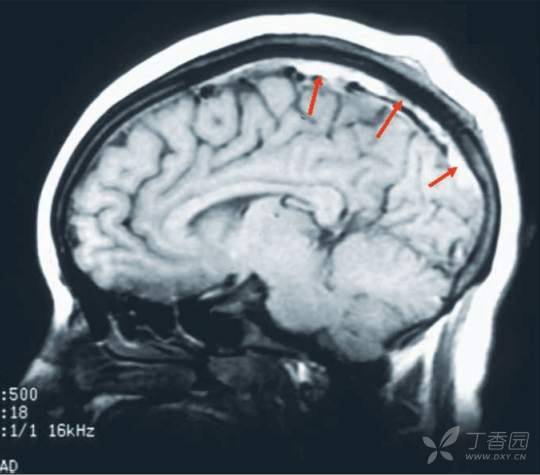

脑静脉血栓形成是颅内压升高的典型原因(图9.16;参见第20章)。患者可能表现为孤立的颅内压升高,因而酷似IIH。早期识别可预防破坏性中风和慢性视乳头水肿引起的视力丢失。

图9.16 矢状位非增强T1加权磁共振成像显示因脑静脉血栓形成导致的上矢状窦高信号。